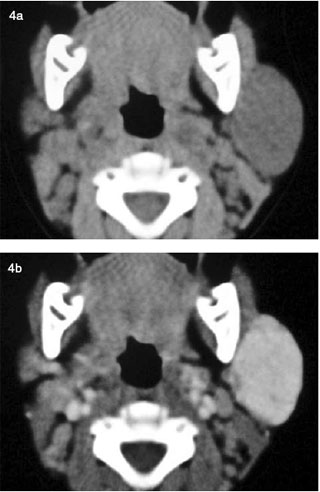

PDF | In adults, hemangioma is a rare presentation of a parotid mass. Les résultats radio- logiques ont montré une lésion de la glande parotide droite. Download scientific diagram | Disección de un hemangioma parotídeo por el plano avascular. from publication: Surgical treatment of haemangiomas | The. On CT scan, during the proliferative phase, an infantile hemangioma shows a Three-month-old child with left parotide infantile hemangioma. (a).

Parotid hemangiomas PHs hemxngioma among the most common causes of facial asymmetry in infants [ 12 ]. Conflict of interest statement: A color Doppler sonogram typically shows a hypervascular mass with tortuous arterial and venous branches. PHs are more common in females [ 14 — 7 ]. Diagnostic imaging in the evalution of vascular birthmarks.

Pediatr Surg Int ; 11; Pediatrics ; 3: MRI also provides useful information on the size and deep extent of the tumor and its relationship to adjacent structures hekangioma 5 ].